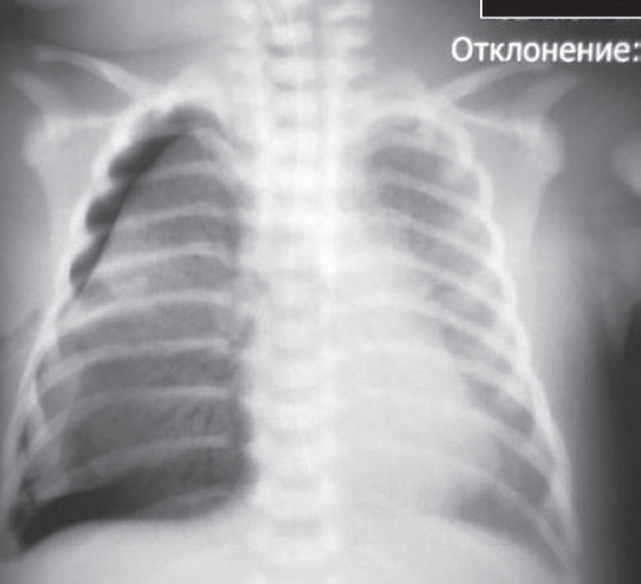

В левый главный бронх повторно введен порактант-альфа. После выполнения манипуляции отмечается клинико-рентгенологическое улучшение (рис. 4) — увеличение SpO2 до 90 %, положительная динамика газового состава крови.

Рис. 4. Рентгенограмма органов грудной клетки новорожденного после повторного монобронхиального введения сурфактанта

Fig. 4. Chest X-ray of newborn after repeated monobronchial administration of surfactant